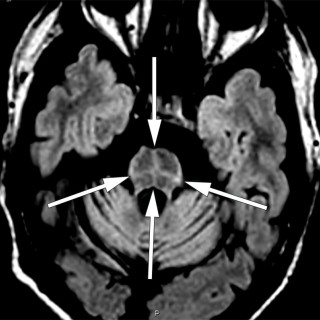

CT-bildene er fra en undersøkelse med opptak uten intravenøs kontrast. Bildet til venstre viser høy attenuasjon i myokard i venstre ventrikkel, og i mindre grad i høyre ventrikkel. Attenuasjonen er tilnærmet lik skjelett i bildet, og tettheten kan passe med forkalkninger. Opptaket er gjort på en spektral-CT, som har økt mulighet for å differensiere mellom ulike vevstyper. Maskinen utnytter de ulike energinivåene i røntgenstrålen, og den kan skille mellom grunnstoffer som jod og kalk utfra absorpsjonsnivået, da begge gir høy attenuasjon. Kalksuppresjon, vist på bildet til høyre (B), bekrefter...